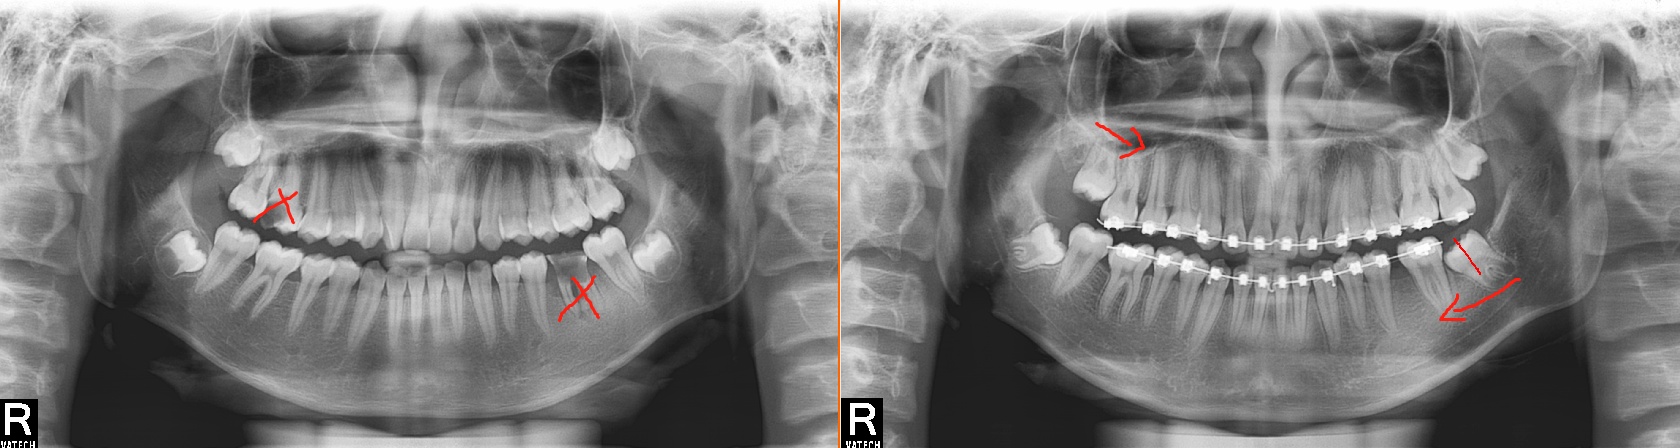

(上图是拔除了龋坏严重的第一磨牙,通知正畸处理,把多余的智齿利用了起来。)

后牙前移,拔除需要根管治疗的或者无法保留的坏牙齿,通过矫正,利用智齿来恢复正常的咬合。

若是第二磨牙严重龋坏,第三磨牙(智齿)还未萌出,也有直接拔掉第二磨牙,不用矫正,第三磨牙直接向前长到第二磨牙的位置并代替它的病例。